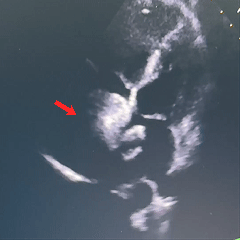

沿房间隔可见封堵装置,沿其周围未测及残余分流。

房室腔正常大小,房室瓣开放活动可。

多普勒超声心动图:各瓣膜血流速度正常。

超声提示:ASD封堵术后,无残余分流。

房间隔可见封堵器回声,位置固定,形态良好。房水平未见残余分流信号。

术后即刻超声检查显示封堵器位置正确、形态良好、夹持稳定,无残余分流。术后第1天和第2天的随访超声进一步显示房间隔可见封堵器回声,位置固定,形态良好,且房水平未见残余分流信号。